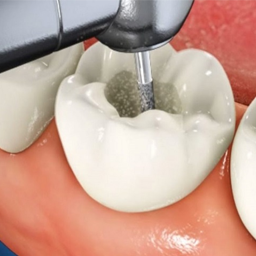

Чихрийн шижин устгах

Ухаангүй байдлаар шүдний цоорлын хэсгийг бүрэн арилгах

Цэнэглэлт эмчилгээ

Биологийн нийцтэй материалаар нарийн дүүргэлт хийх